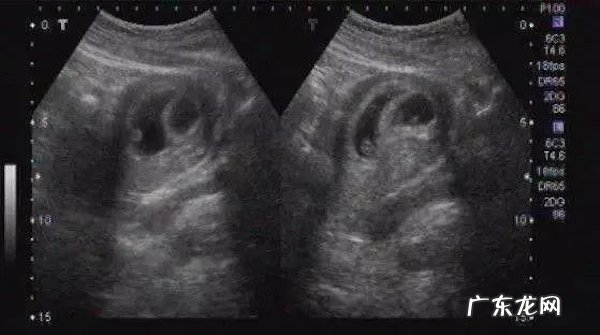

B超能看到性别,得等到长出外生殖器

【清宫表示看男看女 清宫表测男女准吗?】超声看到的是形态上的影像,当胎儿的外生殖器长到可以通过超声看到的程度,就可以进行检查了 。一般需要怀孕3-4月以后了,不过误差也比较大 。更何况,我们国家法律明令禁止孕期看性别,所以,你就别想啦 。